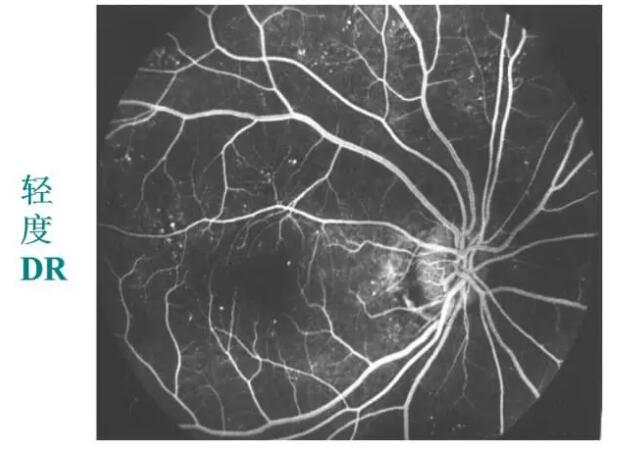

糖网病的眼底表现

微血管瘤

出血斑

渗出

视网膜静脉扩张、动脉变细、小血管闭塞

新生血管

眼底荧光血管造影:更清楚、更敏锐